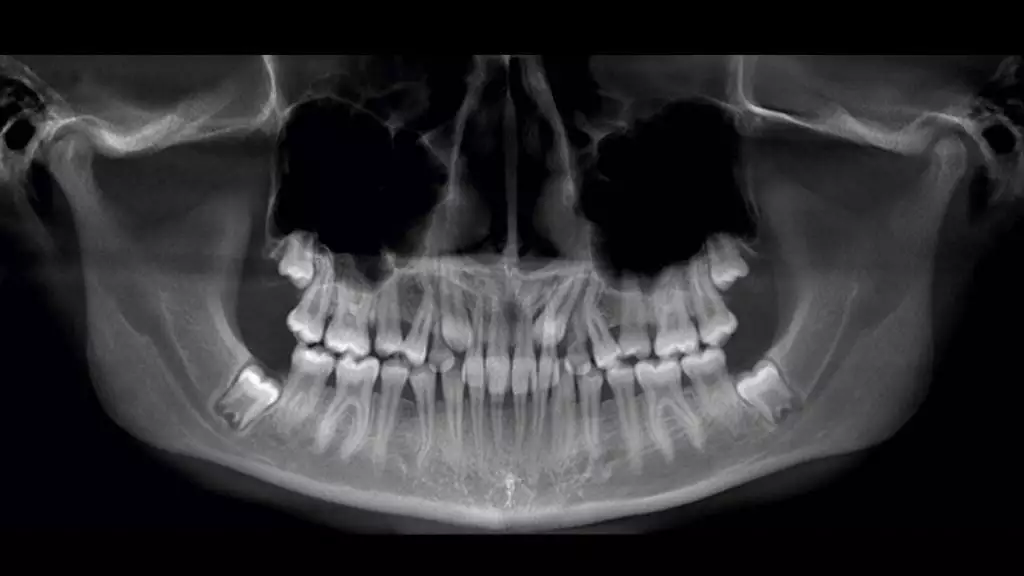

Рентгенографическое исследование является одним из самых распространенных и доступных методов. Оно дает общее представление о состоянии зуба и корневых каналов, но, к сожалению, не всегда позволяет увидеть все искривления и особенности.

Компьютерная томография (КТ) – это более продвинутый метод, который предоставляет трехмерное изображение зуба и его каналов. Это помогает стоматологам лучше составить картину сложной анатомии зуба.

Облитерация каналов — это состояние, при котором корневые каналы зуба сужаются или полностью закрываются. Такое явление может быть вызвано возрастными изменениями, травмами зуба или отложениями вторичного дентина. Диагностика облитерации может быть затруднена из-за сложности визуализации каналов на рентгеновских снимках. Часто для диагностики требуется использование дополнительных методов, таких как компьютерная томография, которая позволяет врачам оценить сложность ситуации.